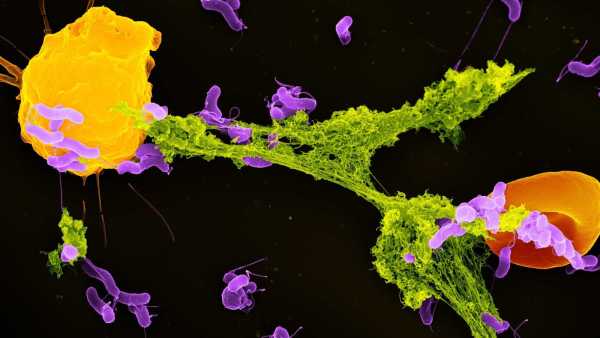

Щоб вивести більш гуманізованих мишей, дослідники спочатку вивели мишей, генетично модифікованих для ослаблення імунної системи. Коли мишам було приблизно 1-2 дні, команда ввела людські стовбурові клітини в серця тварин. Стовбурові клітини, які були вилучені та очищені з пуповинної крові, були здатні перетворитися на будь-який тип імунних клітин.

Потім серця тварин перекачували стовбурові клітини в м’яку губчасту тканину в кістках мишей, відому як кістковий мозок, де зазвичай виробляються імунні клітини. Оскільки миші мали імунодефіцит, людські стовбурові клітини могли легко закріпитися в кістковому мозку.

Після введення людського естрогену миші почали виробляти безліч людських імунних клітин. Серед них були Т-клітини, які безпосередньо атакують мікроби, та В-клітини, що виробляють антитіла, що знищують бактерії та допомагають позначити патогени для знищення.